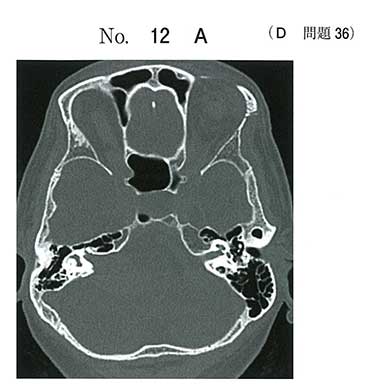

病理は神経鞘腫の典型像です。Antoni Aですね。でも何より、骨状件のCTで右内耳道の漏斗状拡大があり、増強画像で小脳橋角部の内耳道につながる腫瘍ですので、dを選択できないといけません。嚢胞性の神経鞘腫です。うちの学生はできただろうか・・・

聴神経鞘腫もよく嚢胞形成をするという記述が標準放射線医学にあったのを思い出しつつも、なんとなく似てるような気がしてグリブラを選んでしまいました。。。

その時もリング状エンハンスでaを選んだ人が圧倒的に多く、小脳橋角病変は神経鞘腫と髄膜腫を思い出すようしてたので助かりました。

主訴と経過から聴神経腫瘍(神経鞘腫)かなと。画像から小脳橋角部腫瘍と言ったら髄膜腫か神経鞘腫。明らかに髄膜腫ではないから神経鞘腫。で選びました。病理所見は知りませんでした汗。国試テクのringを覚えるなら、小脳橋角部腫瘍もテクとして覚えとくといいでしょう。